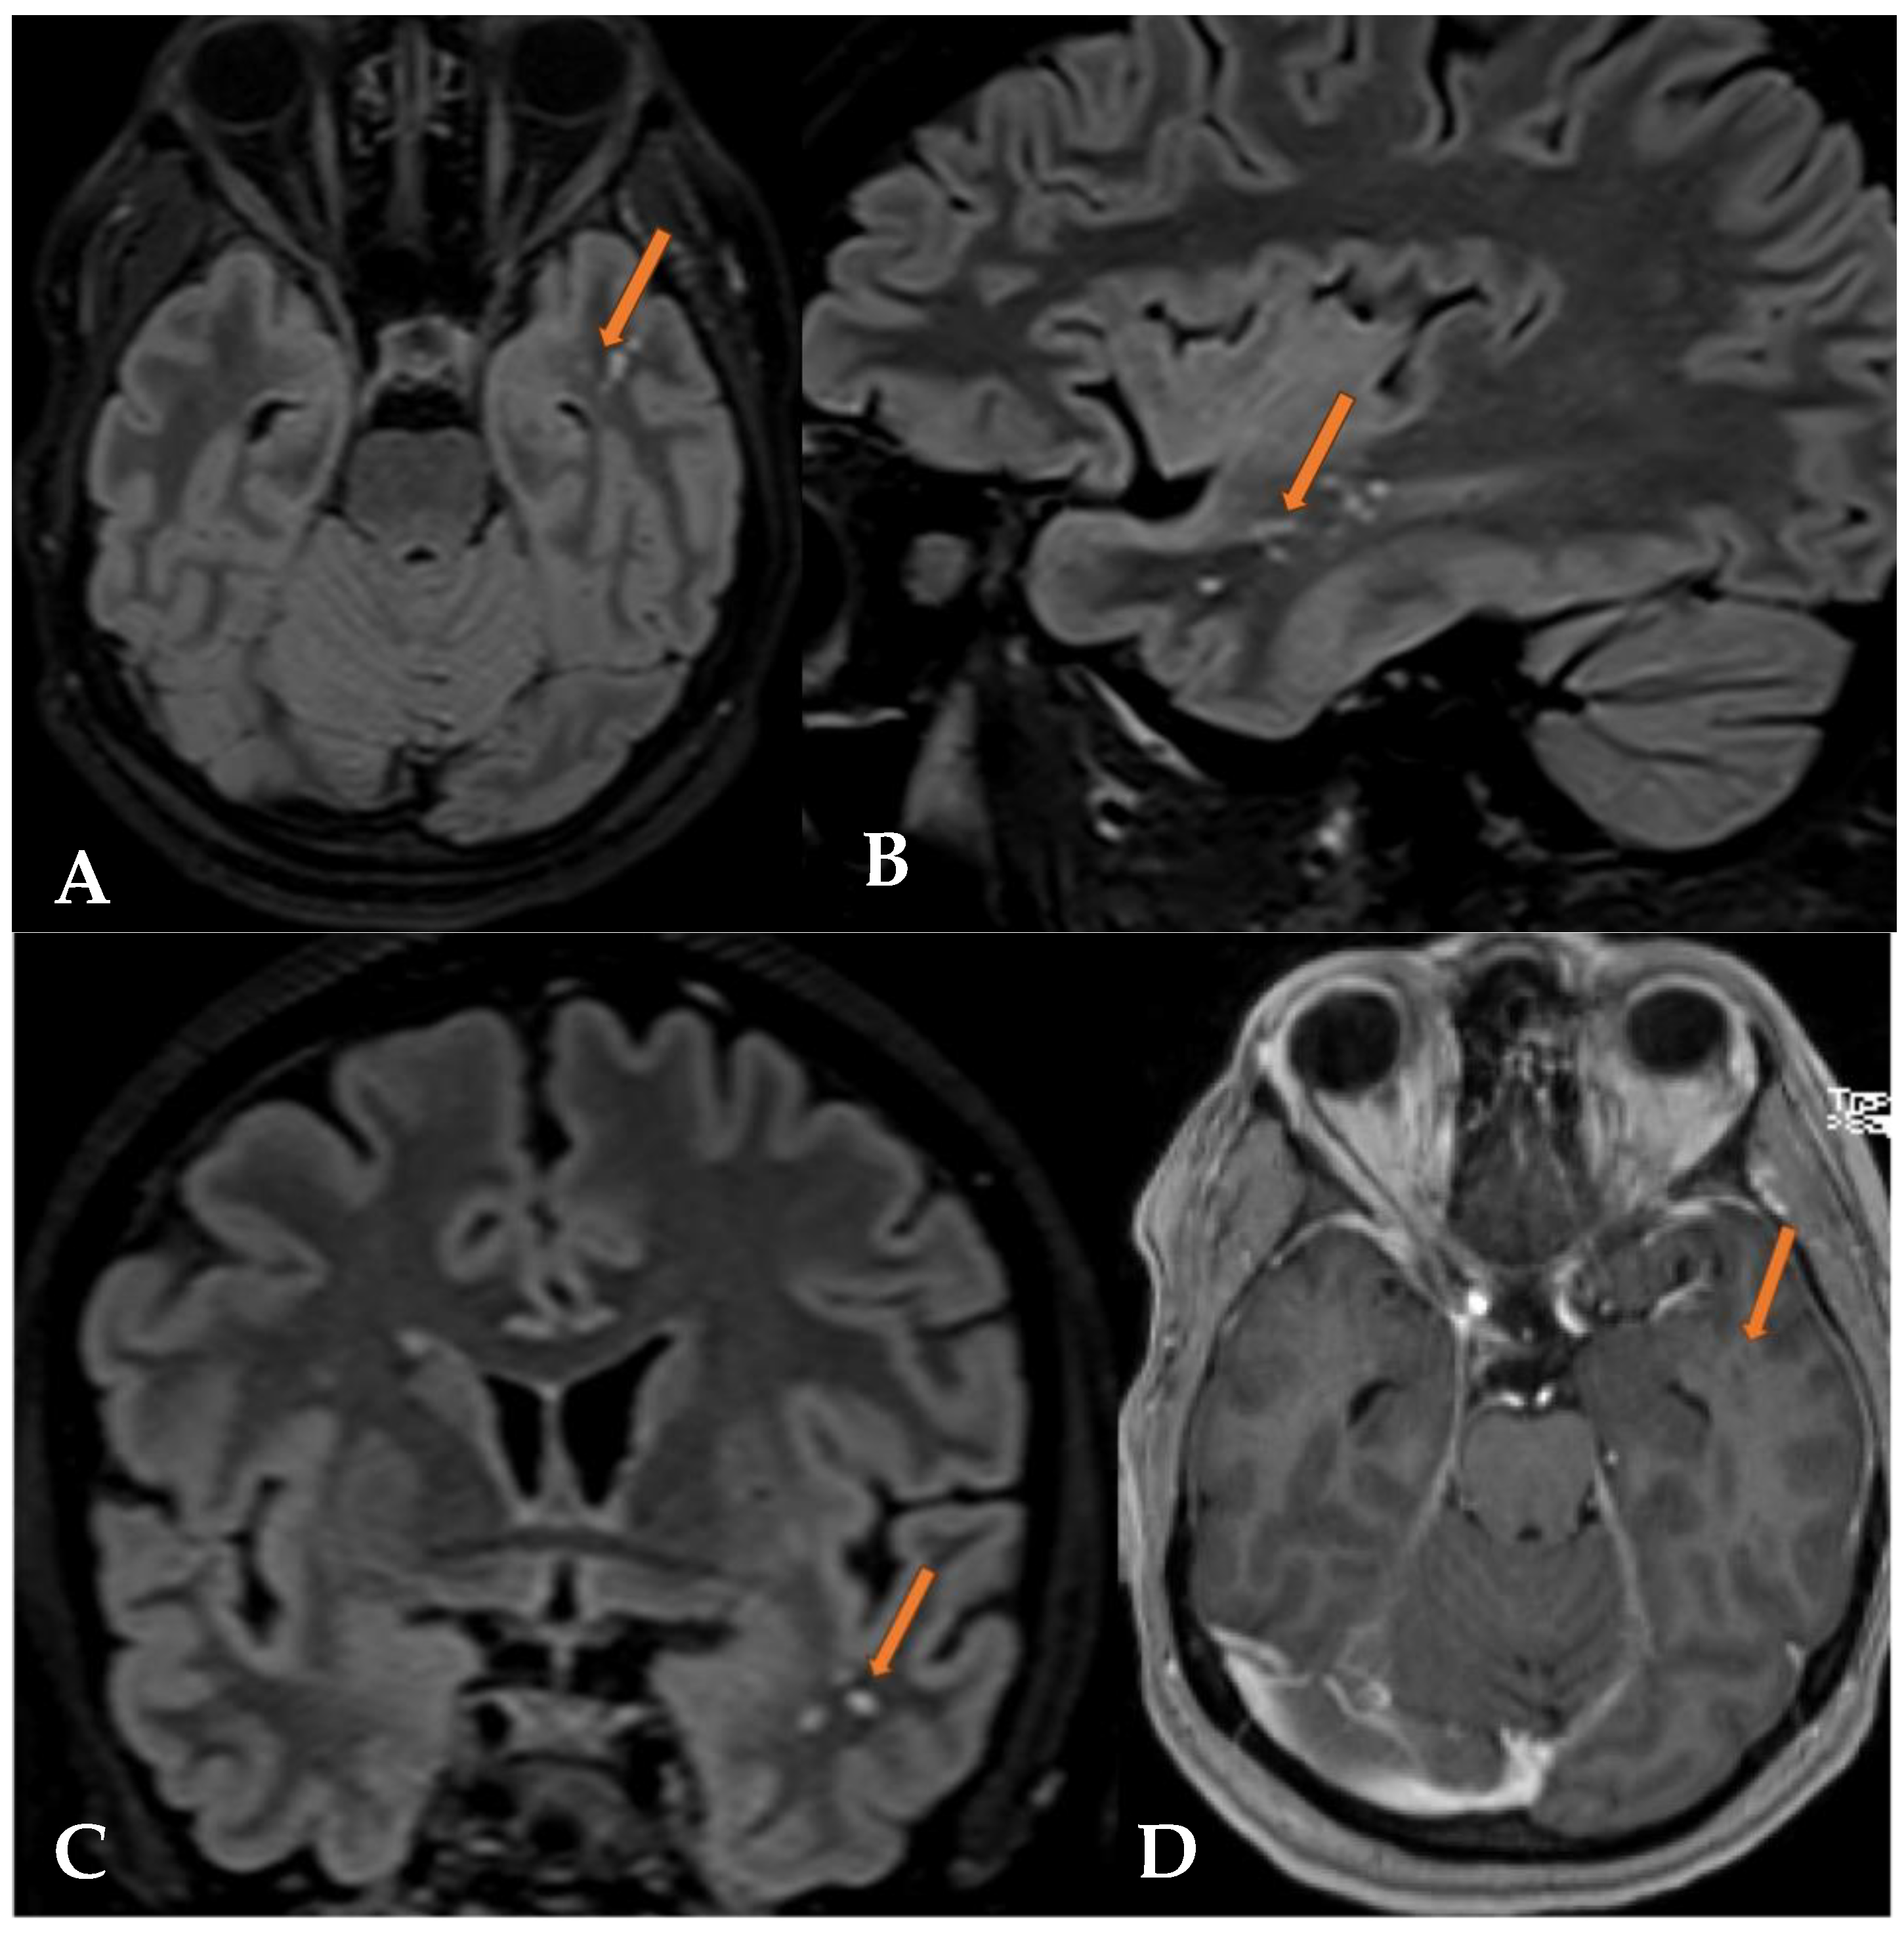

2.1. Case 1